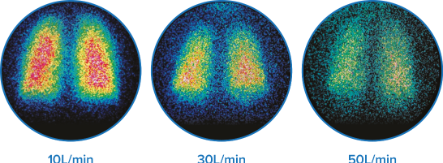

Immagini scintigrafiche rappresentative della deposizione polmonare a portate differenti a 10, 30 e 50 l/min in adulti sani.†6

- Erogazione dal 3,5% al 17% del farmaco ai polmoni, a seconda delle portate del flusso†6

- Risposta broncodilatatrice efficace, anche con un flusso di gas di 50 l/min‡10